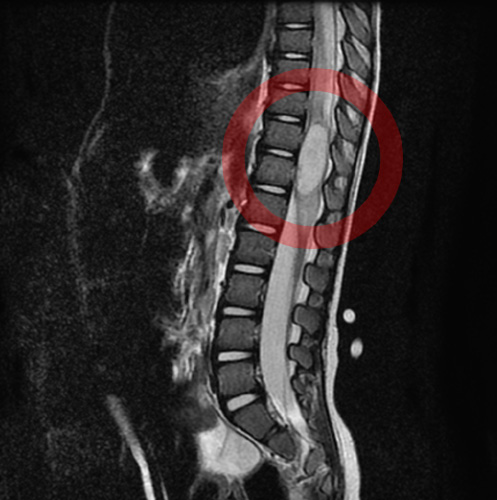

脊柱管という脊髄を収納している腔管の中に発生し、脊髄やその脊髄からでる神経を圧迫する腫瘍のことを総称して脊髄腫瘍と呼びます。

[ 診断 ]

レントゲン、CT検査、MRI検査、PET-CT検査、神経生理検査など